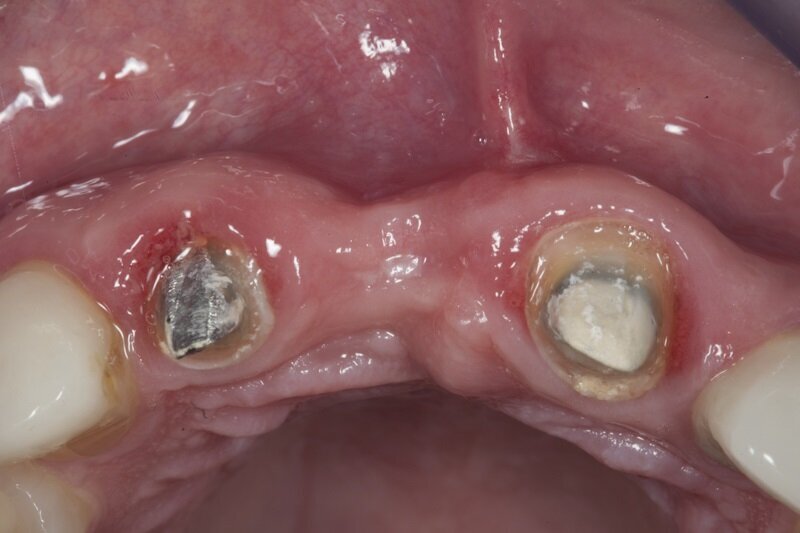

43-letnia pacjentka zgłosiła się do gabinetu w celu uzupełnienia brakującego zęba 11 usuniętego kilka miesięcy temu w innym gabinecie. Brak zostało zaopatrzony czasowym mostem wspartym na zębach 12 i 21. Pacjentka była ogólnie zdrowa. Badanie przedmiotowe wykazało duży zanik kostny przedsionkowo, płytki przedsionek jamy ustnej i niski przyczep wędzidełka wargi górnej (Ryc. 1 i 2). Badanie CBCT wykazało znaczny zanik pionowy wyrostka (Ryc. 3).

Na podstawie uzyskanych danych zasugerowano pacjentce etapowe rozwiązanie zaistniałej sytuacji, na co uzyskano zgodę. Pierwszy etap obejmował frenulotomię i westibiloplastykę w celu uzyskania poprawy zastanych warunków pod względem tkanek miękkich. Zaplanowano dowierzchołkowe przesunięcie płata śluzówkowego z pozostawieniem okostnej. Zabieg przecięcia błony śluzowej przeprowadzono przy użyciu lasera Er:YAG przy następujących ustawieniach: VLP 120 mJ, 20 Hz, a następnie przesunięty dowierzchołkowo płat błony śluzowej wraz z przyczepami mięśni przyszyto szwami materacowymi Prolene 5.0 do okostnej (Ryc. 4). Następnie, przy użyciu głowicy Genova i lasera Nd:YAG o parametrach: MSP, 0,5 W, 20 Hz dokonano naświetlenia rany w 4 miejscach po 60 s na punkt (Ryc. 5-7).